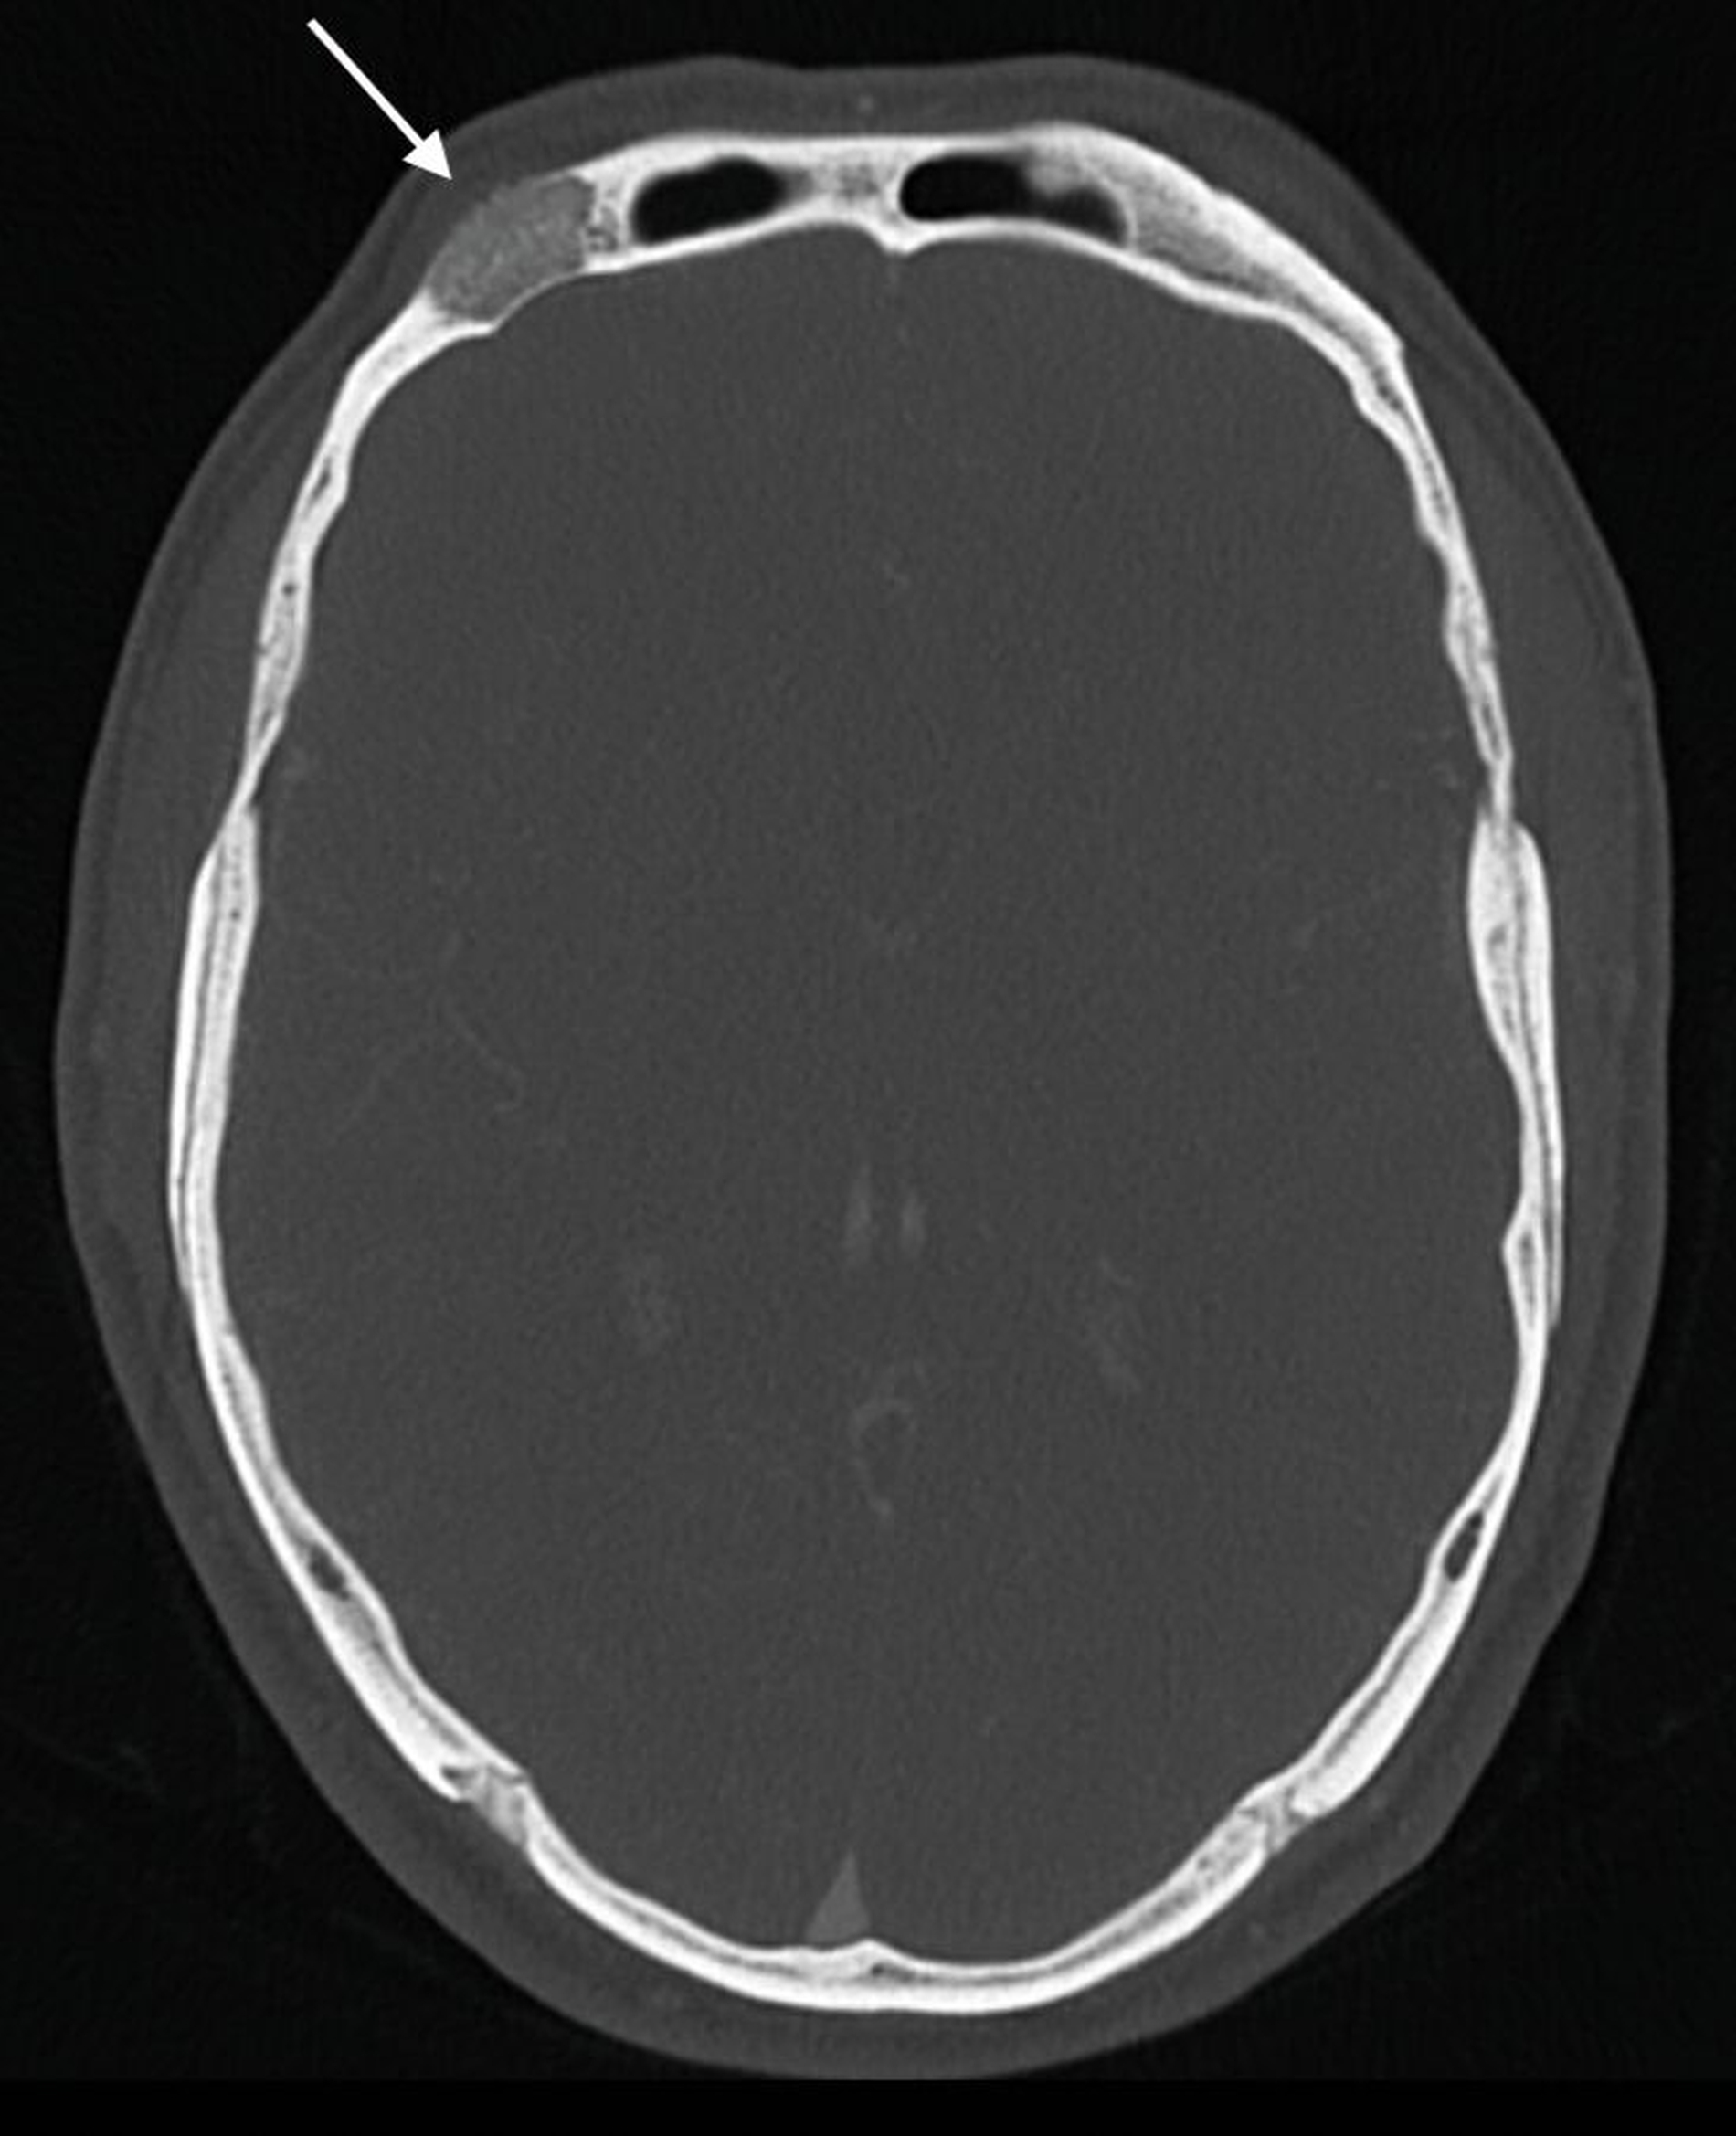

In der klinischen Untersuchung zeigte sich eine harte, unverschiebliche und gut begrenzte Raumforderung. Die sonografische Untersuchung erbrachte keinen wegweisenden Befund, so dass eine Computertomografie (CT) des Mittelgesichts mit Kontrastmittel durchgeführt wurde. Hier konnte eine supraorbital im Os frontale gelegene, glatt begrenzte Raumforderung mit feingranulierter Verkalkung und einer Ausdehnung von circa 2 cm x 2 cm x 1 cm dargestellt werden.

Diese überschritt nach ventral bereits die Kortikalis und wurde nach dorsal nur noch durch eine dünne Knochenlamelle von den Meningen abgegrenzt. Insgesamt passte der Befund CT-morphologisch zu einem Kalottenhämangiom, differenzialdiagnostisch war auch ein Eosinophiles Granulom möglich (Abbildungen 2 bis 4).

Die Darstellung intraossärer Befunde gelingt mittels Sonografie jedoch nicht. Eine Magnetresonanztomografie mit Kontrastmittel oder auch eine MR-Angiografie können die Diagnostik ergänzen. Die Computertomografie (CT) sollte wegen der Strahlenbelastung bei weichteiligen vaskulären Anomalien nicht standardmäßig angewandt werden [Sadick et al., 2018]. Bei Läsionen, die intraossär liegen, weist diese jedoch möglicherweise eine genauere Darstellung, gerade in Bezug auf den umliegenden Knochen, auf.

Im Bereich der Stirn kann mittels CT eine exakte Abgrenzung der Raumforderung nach intrakraniell, zur Orbita und zum Sinus frontalis erfolgen [Isaac et al., 2018]. Ein weiterer Vorteil der CT liegt darin, dass bei ausgedehnten knöchernen Läsionen mit dem CT-Datensatz eine Rekonstruktion mit einem patientenspezifischen Implantat (PSI) geplant werden kann. Als dritter Arm der apparativen Diagnostik steht die DSA zur Verfügung. Bei klinischem und radiologischem Verdacht auf eine intraossäre vaskuläre Anomalie sollte auf eine präoperative Biopsie aufgrund der Gefahr einer massiven Blutung verzichtet werden [Isaac et al., 2018].